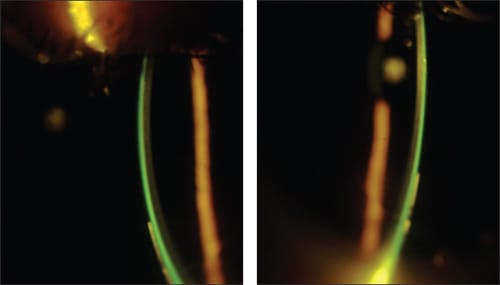

The lenses aligned with the cornea, cleared the limbus, and landed on the sclera evenly. The patient reported that she could barely feel the lenses and gave them a 9-out-of-10 comfort rating. Upon dispensing, the lenses fit well (Figures 9 and 10) and provided excellent vision. She has now been wearing this contact lens design for two years with less than 0.50D change in refraction.

Figures 9 and 10. Case 4 optic section of the lenses showing alignment over the central cornea.

The lenses were ordered 1.25D flatter base curve in the right eye and 0.75D flatter base curve in the left eye. They were also ordered with a 1.00D flattening to the peripheral curve system to eliminate the minor blanching noted. Flatter lenses were then chosen with a base curve of 8.55mm, power of −1.00D, OAD of 13.1mm, and 1.00D flat peripheral curves for the right eye and a base curve of 8.35mm, power of −1.75D, OAD of 13.1mm, and 1.00D flat peripheral curves. (Figures 15 and 16)

Figures 15 and 16. Optical coherence tomography images of the lenses in Case 5. The images demonstrate the alignment of the lenses with the smallest amount of clearance between the lens and the cornea.